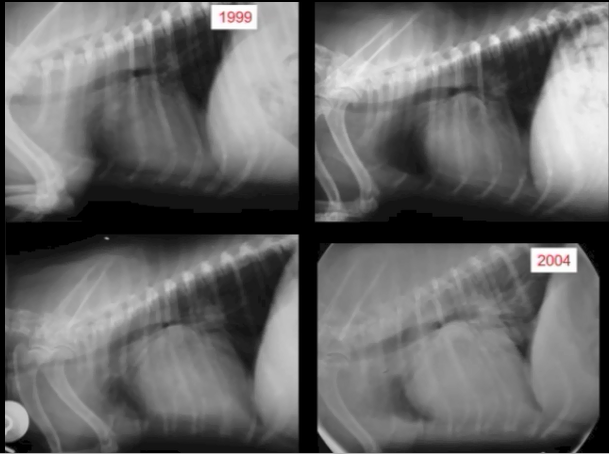

• VHS measurements to detect enlargement

Cardiologists use x-rays to evaluate the size and shape of the heart in

order to assess the severity of MVD.

The Vertebral Heart

Size or Scale or Sum (VHS) is an objective means of measuring

heart size.

As

the x-ray image above shows, using calipers, they

measure the length (from the apex to the bottom of the left mainstem) and width

(at

its widest point perpendicular to the lemgth measurement) of the heart

on a lateral x-ray and compare those dimensions

to the number of veterbrae from T4 to T12, to calculate the VHS value. Since

the dog's own vertebrae are used for comparison, each VHS value is

normalized to the dog's overall body size.

See

this

YouTube video for details. A diagram showing how the VHS is calculated

is

here. This is called the Buchanan VHS method, devised

by Dr. James W.

Buchanan, a pioneer in the research of MVD in cavaliers, in

1995. See his

1995 article.

The VHS is not intended to diagnose CHF. It's purpose is to enable veterinarians to more accurately determine enlargement of the heart (called cardiomegaly or dilation) and the progression at which the enlargement is occurring, which usually is due to MVD. However, since MVD normally initially causes only the left atrium (LA) to enlarge, the VHS method is not precise enough to measure only the size of the LA. See for example, the x-ray at left, which shows that the VHS measurements entirely miss the bulbous enlarged LA in the upper right corner of the heart. (Image from Hezzell, 2018.)

The VHS method is most effective when it is used to compare two x-rays of the same dog's heart, taken over time, to see if the later x-ray's VHS value is higher than the earlier one, thus indicating that an enlargement of the heart has occurred. Therefore, once an MVD murmur is first detected, it is advisable to obtain an initial set of chest x-rays (called a "baseline" set) for comparison with subsequent x-rays once progression of the MVD is suspected.

An increase in VHS value of >0.1 per month over six months or more, in combination with a VLAS value >3.0, (see VLAS below) is evidence that the patient's heart has enlarged enough to classify it in Stage B2.

Some veterinary cardiologists have used the VHS method to try to determine breed-specific and even species-wide ranges of heart sizes of dogs with healthy (non-MVD) hearts, rather than just to compare VHS values in periodic x-rays of the same dog. There are published breed-specific studies of ranges of VHS values for dogs' healthy hearts for dozens of breeds.

The VHS values of cavaliers which do not have any heart enlargement can vary widely. In a 2001 study of 20 CKCSs and a 2005 study of 50 of them, researchers found that the normal range of VHS values for cavaliers was from 10.0 to 11.7. In an October 2018 article, a cavalier with a normal-sized heart with a VHS value of 11.9 was reported. In an October 2023 article in which 167 CKCSs with normal-sized hearts were examined, their VHS values ranged from 8.5 to 12.5. These wide ranges of normal-sized VHS values make efforts to diagnose heart enlargement with a single set of x-rays pointless, unless the VHS value is above 12.5.

In the 2016 EPIC Study, its lead investigators included in their arbitrary definition of enlarged hearts in MVD-affected dogs, a maximum VHS value of 10.5 for all dogs of all breeds and mixed breeds. Specifically, the EPIC Study definition of an enlarged heart included: "... radiographic evidence of cardiomegaly (vertebral heart sum (VHS) > 10.5)." This definition was an absurdity for at least three reasons: (1) VHS values of cavaliers with MVD-clear hearts have been reported as high as 11.9, and other breeds have average VHS values for healthy hearts in excess of 10.5; (2) VHS values of healthy hearts are necessarily breed-specific because different breeds have different sizes of hearts and even different sizes of vertebrae and intervertebral disk spaces; and (3) the best use of the VHS method is to compare VHS values of the same dog in periodic x-rays over time.